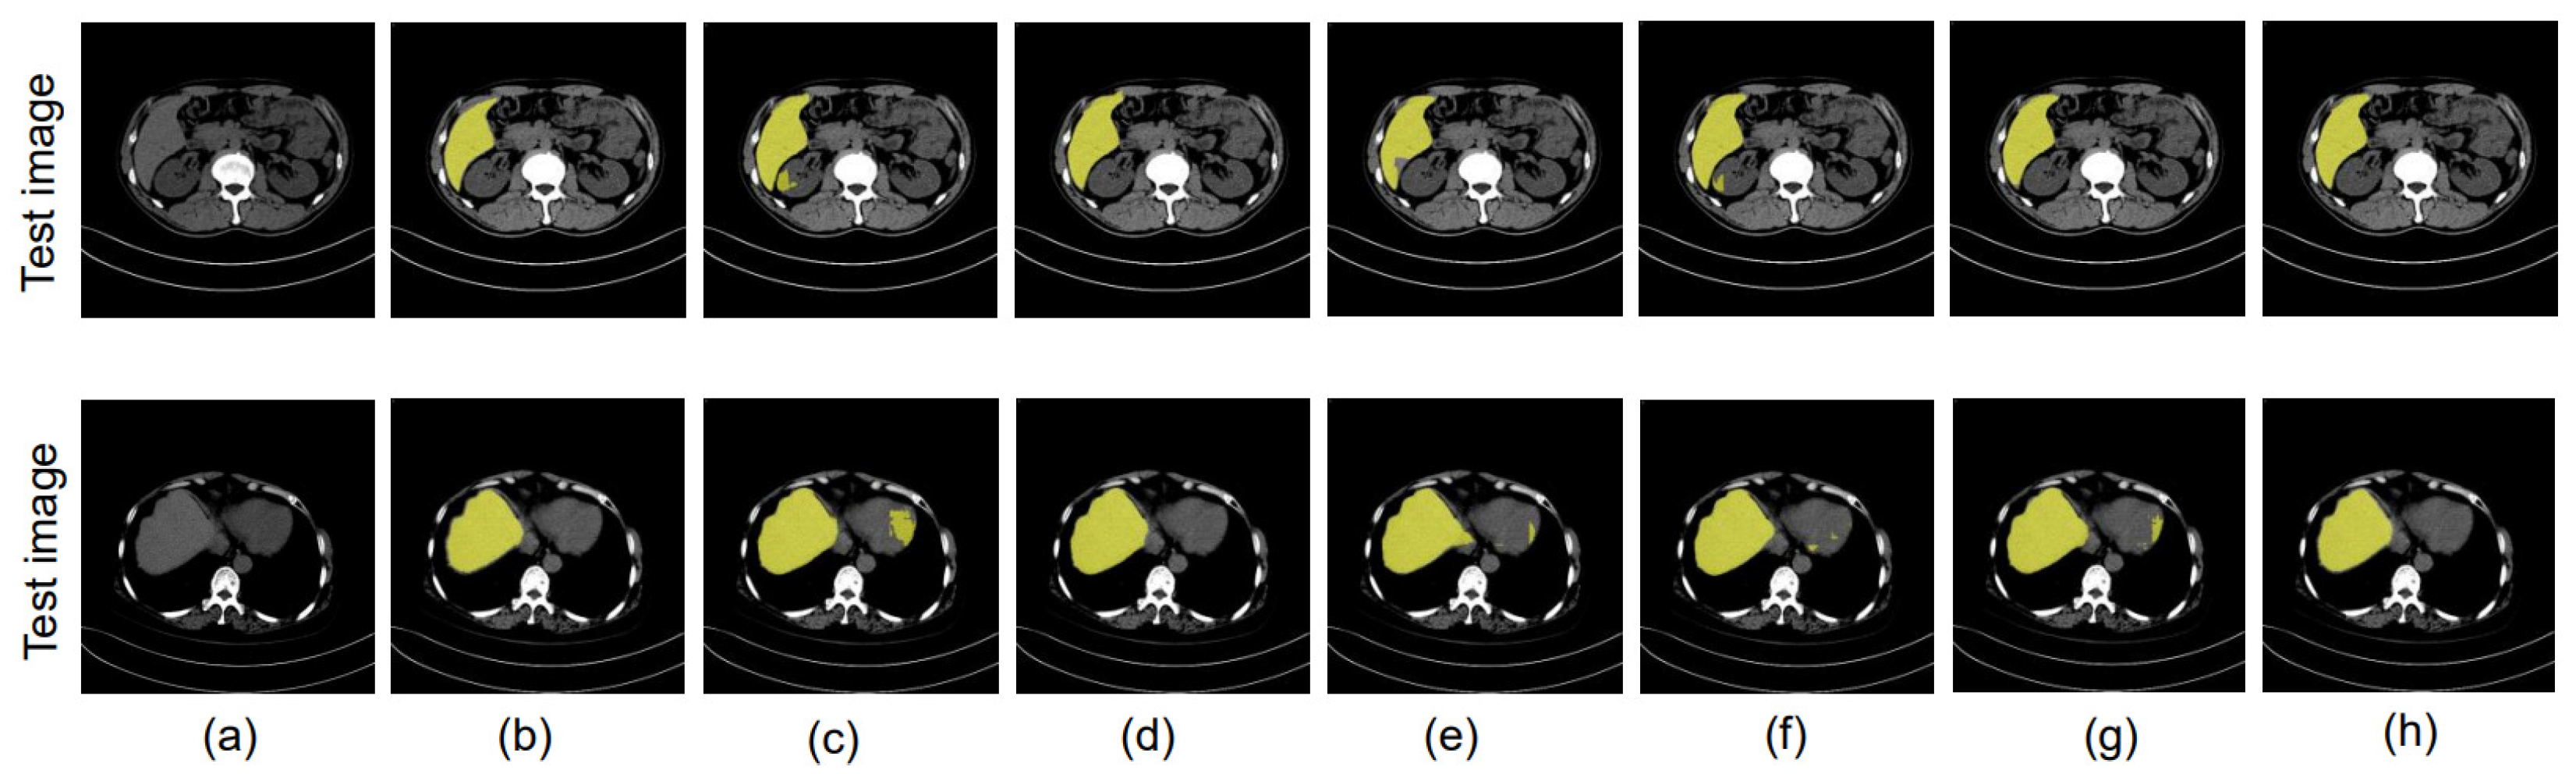

4.8. Ablation Study

4.8.1. Different Datacenter and Same Phase

4.8.2. Same Datacenter and Different Phase

4.8.3. Different Datacenter and Different Phase